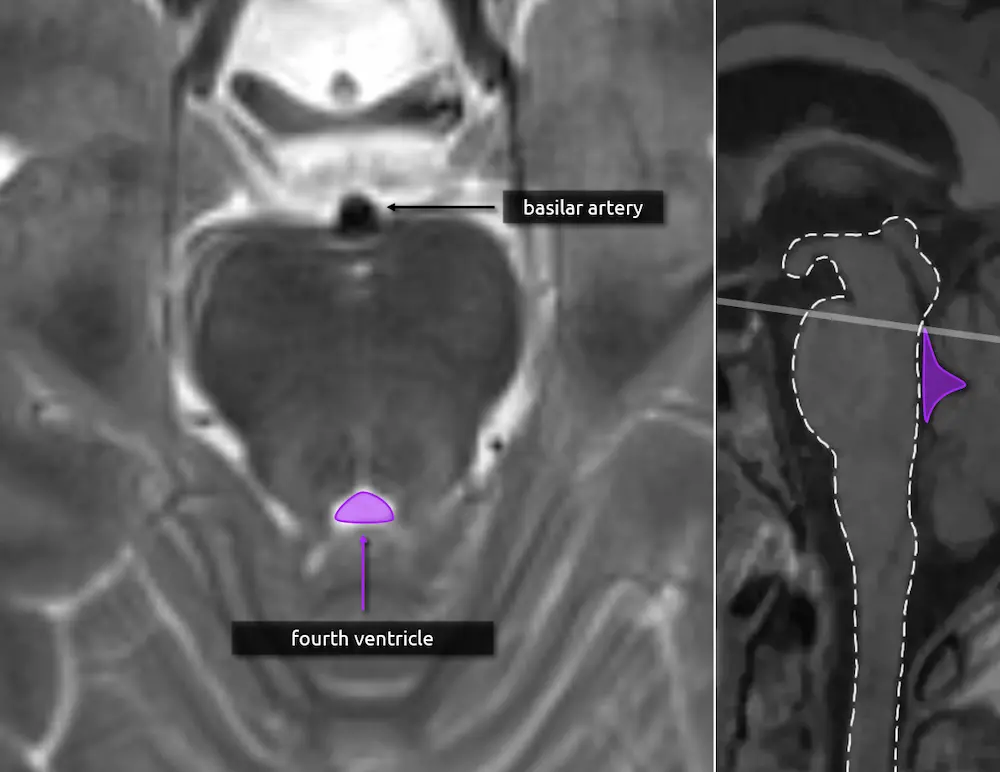

The pons' bulbous contour in the sagittal plane can also be seen on axial cuts. The "Mickey Mouse" appearance of the midbrain is no longer visible.

1. Fourth ventricle

The triangular CSF space posterior to the pons is the fourth ventricle. It should be seen on every head CT or brain MRI and, if it is not, there is likely pathology. Effacement of the fourth ventricle may be an early sign of mass effect, either due to a lesion or edema.

2. Basilar artery

The basilar artery courses along the surface of the pons. It should always be dark on a T2-weighted image. A bright basilar artery is a sign that blood has stopped moving or is moving slowly (i.e. "loss of flow void"), suggesting an occlusion.

View the images on the right to see how the caliber of the fourth ventricle changes as you scroll up and down. The fourth ventricle's caliber is largest at the mid aspect of the pons.